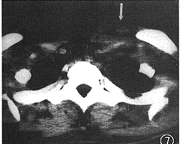

图7 同图5病例,左锁骨上淋巴结肿大(↑)

3. 胸部以外的影像表现:颈部淋巴结肿大2例,合并锁骨上淋巴结肿大(图7)。淋巴结融合肿块最大3.5 cm× 5.5 cm。腹膜后淋巴结肿大1例,腹部CT见后腹膜有多个肿大淋巴结,最大直径1.8 cm,增强扫描淋巴结边缘有环形强化(图8)。